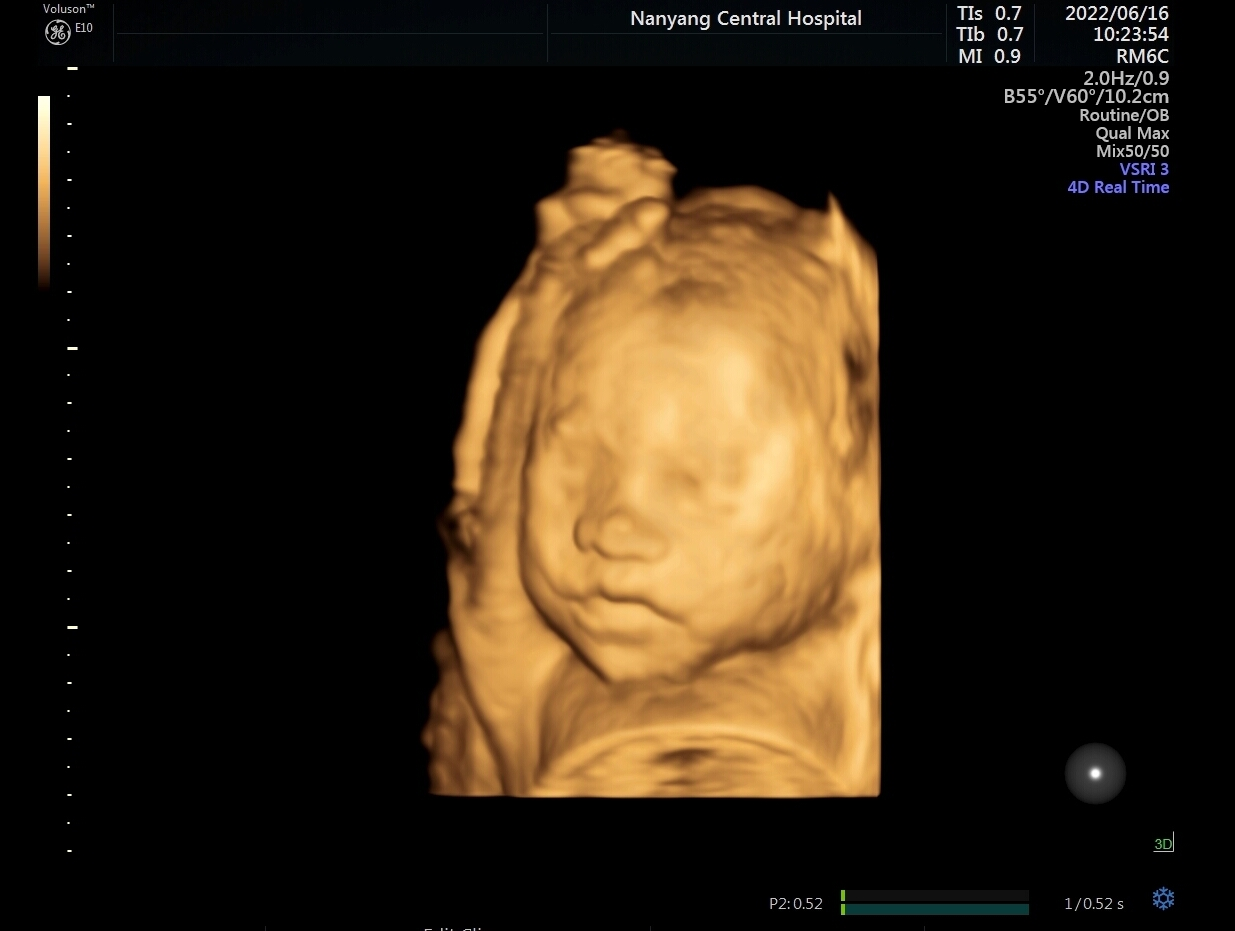

不管是黑白超还是彩超,我们看的图像都是平面的,也就是二维的,超声医师是通过二维切面来观察器官内部的结构。除了基础的二维成像,还有三维、四维重建成像,就是将无数个二维切面组合起来形成一个立体图像,可以更直观、更形象的观察目标结构。

宫内胎儿四维图像